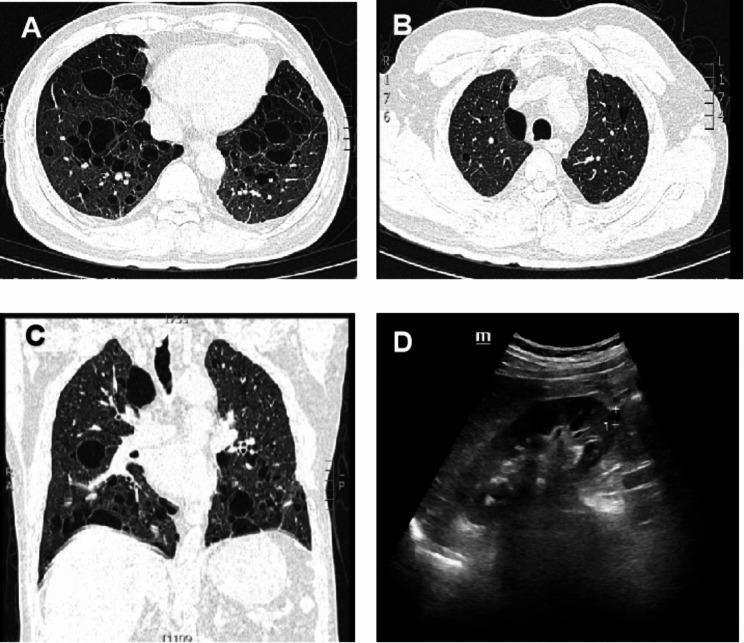

We report a rare case of Sjogren's syndrome complicated with Birt-Hogg-Dubé syndrome (BHDS) not previously mentioned in the literature. Further, there is insufficient evidence linking the two diseases. Here, we review existing diagnostic algorithms for diagnosing diffuse cystic lung disease and provide new insights. The patient initially complained of thirst and dry eyes for ten years, and gradually developed shortness of breath. After admission, physical examination showed five missing teeth, decreased respiratory sounds in both lower lungs, and Velcro rales. Computed tomography showed multiple thin-walled cystic lesions in both lungs. Initial xerophthalmia and labial gland biopsy seemed to reveal a pulmonary cystic change associated with Sjogren's syndrome. Before discharge, a rash suspected to indicate a fibrofollicular tumor in the neck was observed, and then FLCN variant has been found. The challenges how to clarify the diagnosis of DCLD causes are discussed.

我们报告了一例以前文献中未提及的干燥综合征合并 Birt-Hogg-Dubé 综合征(BHDS)的罕见病例。此外,这两种疾病之间的关联证据不足。在这里,我们回顾了现有的弥漫性囊性肺病诊断算法,并提供了新的见解。患者最初抱怨口渴和干眼症十年,逐渐出现呼吸困难。入院后,体格检查显示五颗缺牙,双下肺呼吸音减弱,Velcro 啰音。计算机断层扫描显示双肺多发性薄壁囊性病变。最初的干眼症和唇腺活检似乎显示与干燥综合征相关的肺囊性改变。出院前,观察到颈部疑似提示纤维滤泡瘤的皮疹,随后发现 FLCN 变异。讨论了如何阐明 DCLD 病因诊断的挑战。